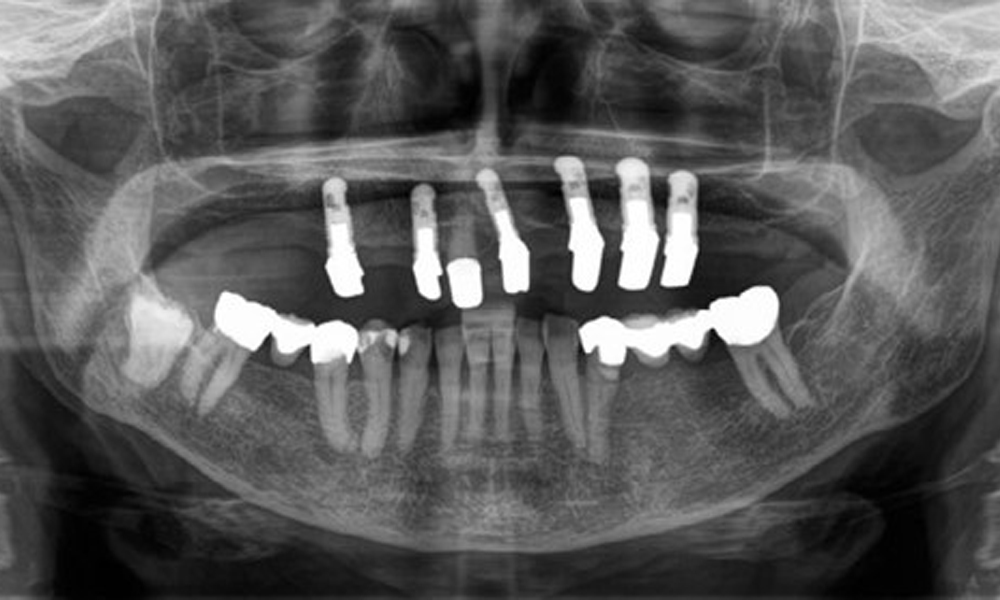

Radiologischer Befund

Aus dem radiologischen Befund zeigt sich ein teilbezahntes Gebiss mit Implantaten im Oberkiefer an 15, 13, 21, 23, 24, 25 und einer Teleskopkrone 11. Im Unterkiefer sind suffiziente Brücken von 37–34 und 45–47 vorhanden. 48 ist retiniert. 43 distal besteht der Verdacht auf Sekundärkaries und 44 mesial Verdacht auf Sekundärkaries. 44 ist mit einer nicht röntgenopaken Unterfüllung versorgt.

Es zeigt sich ein generalisierter horizontaler Knochenabbau von ca. 10–30 % und lokalisiertem vertikalen Knochenverlust an 22 und 42. (Abb. 5)

Panoramaschichtaufnahme. Es zeigt sich ein generalisierter Knochenabbau zwischen 10-30%. 44 und 43 haben einen radiologischen Verdacht auf eine Sekundärkaries.

Abb. 5: Panoramaschichtaufnahme. Es zeigt sich ein generalisierter Knochenabbau zwischen 10–30 %. 44 und 43 haben einen radiologischen Verdacht auf eine Sekundärkaries.